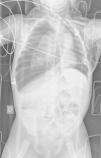

Figura 2.

Corte sagital de TC en el que se aprecia la presencia de aire en el canal raquídeo en toda su longitud, disecando por completo las estructuras nerviosas.